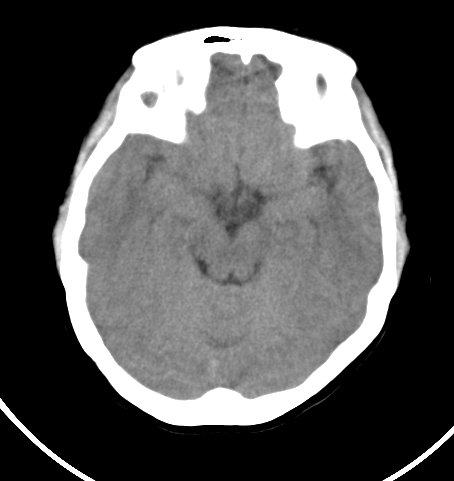

病人女 35岁 自述头晕 头痛

双侧基底节区及右侧丘脑区多发点状钙化,周围未见水肿及占位征象.余未见明显异常.考虑:脑囊虫病<囊虫的退变或死亡期>请结合有无相关病史.

以下是引用苯小孩在2007-4-20 15:47:00的发言:[br]双侧基底节区及右侧丘脑区多发点状钙化,周围未见水肿及占位征象.余未见明显异常.考虑:脑囊虫病<囊虫的退变或死亡期>请结合有无相关病史.

颅内有散在钙化

脑囊虫病理性钙化。